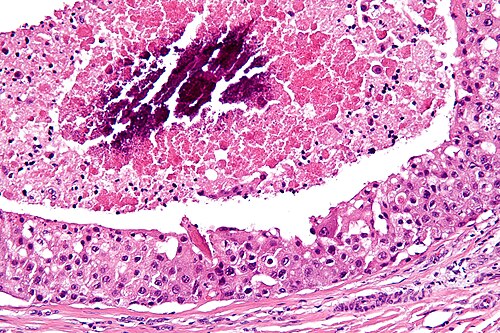

66 year old man, parotid mass.

Right parotid salivary gland.

Intermediate magnification. H&E stain.